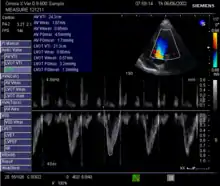

Echocardiography

Echocardiography is a non-invasive method of quantifying cardiac output using ultrasound. Two-dimensional (2D) ultrasound and Doppler measurements are used together to calculate cardiac output. 2D measurement of the diameter (d) of the aortic annulus allows calculation of the flow cross-sectional area (CSA), which is then multiplied by the VTI of the Doppler flow profile across the aortic valve to determine the flow volume per beat (stroke volume, SV). The result is then multiplied by the heart rate (HR) to obtain cardiac output. Although used in clinical medicine, it has a wide test-retest variability.[8] It is said to require extensive training and skill, but the exact steps needed to achieve clinically adequate precision have never been disclosed. 2D measurement of the aortic valve diameter is one source of noise; others are beat-to-beat variation in stroke volume and subtle differences in probe position. An alternative that is not necessarily more reproducible is the measurement of the pulmonary valve to calculate right-sided CO. Although it is in wide general use, the technique is time consuming and is limited by the reproducibility of its component elements. In the manner used in clinical practice, precision of SV and CO is of the order of ±20%.